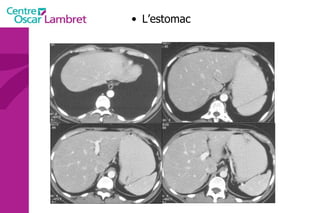

Tube Digestif L’Estomac

Tube Digestif L’estomac : Situation dans l’hypocondre gauche et l’épigastre. taille variable (selon  patient et  degré de remplissage) 3 moyens d’attache. Paroi fine et régulière  < 10 mm ( fiable si estomac distendu) grande courbure = sous phrénique G pylore,le Cardia et la petite courbure.

L’estomac Il est très vascularisé par des branches qui proviennent du tronc cœliaque issu de l’aorte.

Différentes parties de l’estomac cardia Petite courbure Grande   courbure pylore antre fundus Antre pylorique duodénum Poche à air   gastrique corps

L’estomac